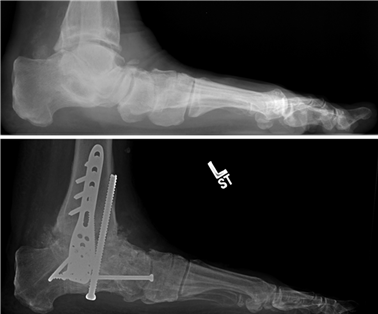

Weight-bearing anteroposterior (AP), lateral, and sesamoid axial radiographs are mandatory. On the AP view, the surgeon measures the Hallux Valgus Angle (HVA, normal < 15°), the Intermetatarsal Angle (IMA, normal < 9°), and the Distal Metatarsal Articular Angle (DMAA). The lateral view is scrutinized for Meary's angle (talo-first metatarsal angle) to identify midfoot collapse, as well as the presence of dorsal osteophytes indicative of hallux rigidus. The sesamoid axial view is critical for assessing the degree of sesamoid subluxation and the integrity of the crista.

The Lapidus Arthrodesis (First TMT Fusion)

For severe deformities or hypermobility, the Lapidus procedure provides robust stabilization of the medial column. A dorsal or medial incision is utilized over the first TMT joint. The extensor hallucis longus (EHL) is retracted dorsally, and the tibialis anterior tendon is identified and protected at its insertion on the medial cuneiform and first metatarsal base. The TMT joint capsule is incised, and the joint is thoroughly debrided of all articular cartilage using a combination of osteotomes, curettes, and a high-speed burr.

To achieve multiplanar correction, the surgeon must address the sagittal, coronal, and transverse planes. The first metatarsal is plantarflexed to restore the longitudinal arch, rotated out of pronation to realign the sesamoids, and translated laterally to close the IMA. Subchondral drilling or feathering is performed to optimize the biological environment for fusion. Fixation is traditionally achieved with two or three crossed solid or cannulated screws (typically 3.5mm or 4.0mm). Recently, plantar or medial locking plates have gained immense popularity due to their superior biomechanical construct, allowing for earlier weight-bearing. Bone graft or orthobiologics may be packed into the arthrodesis site to stimulate osteogenesis.